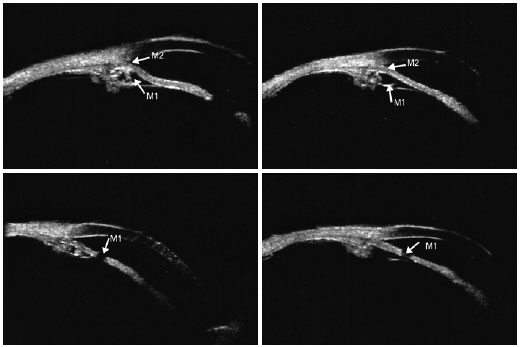

Ultrasound biomicroscopy (UBM) of the angles confirmed the presence of very narrow or opposed iridotrabecular angles with multiple cysts at the iris root and iridociliary junction in all meridians. Laser iridotomies confirmed patency in both eyes (Figure 3).